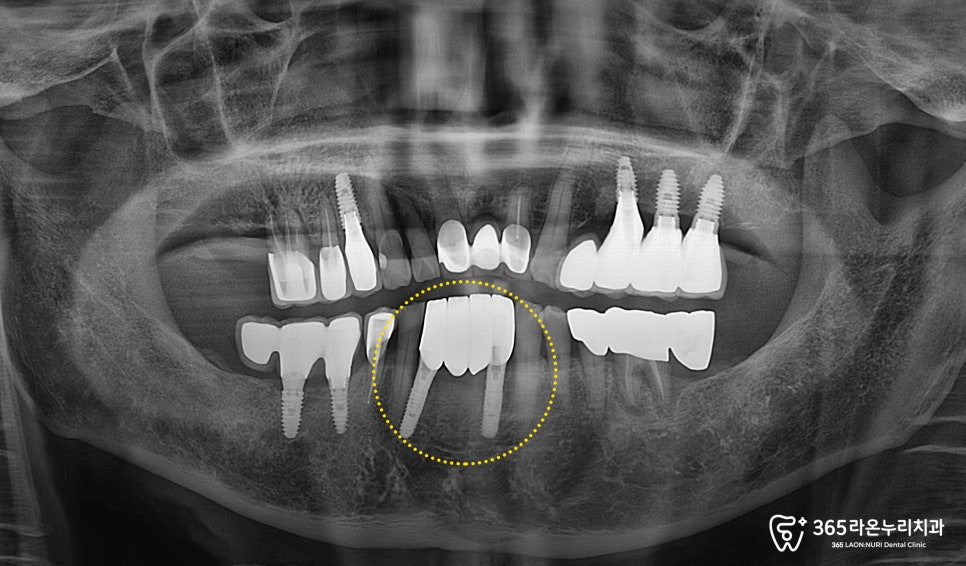

눈으로도 심한 아랫니 흔들림이 관찰되며,

동요도 검사에서도 높은 흔들림으로

mob(+++) 확인됩니다.

실제로 만졌을 때,

자연 발치가 이루어질 정도로

앞 뒤로 심하게 흔들리고 있었습니다.

치근단 사진에서도 심한 골흡수 양상이 나타나,

빠른 발치가 필요하다고 판단하게 되었습니다.

아래 앞니 브릿지 제작을 위해

두 개의 임플란트 픽스처를

의도한 곳에 잘 식립한 모습입니다.